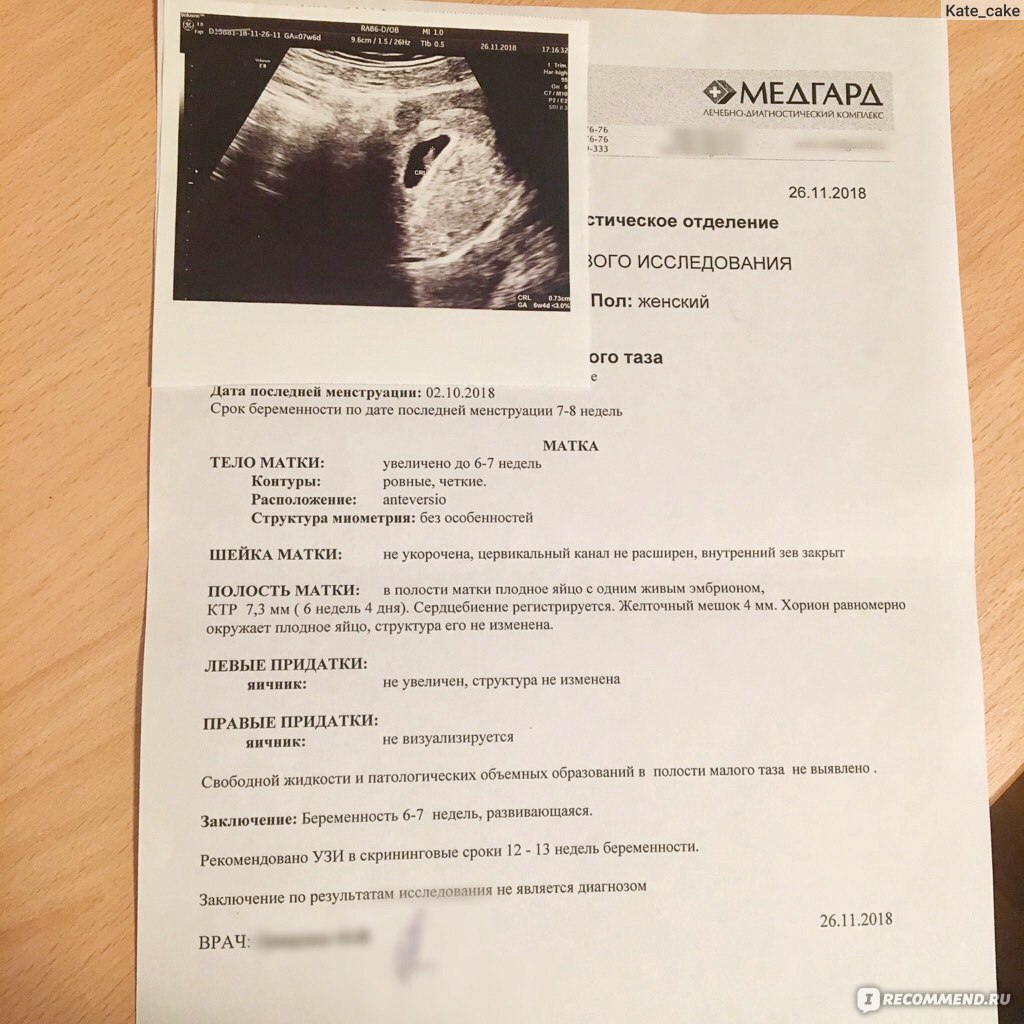

Маточная беременность раннего срока, плодное яйцо

На 4 неделе может быть видно плодное яйцо, но эмбрион еще не всегда визуализируется.

На каком сроке можно увидеть плодное яйцо на УЗИ

Информативность узи на ранних сроках беременности